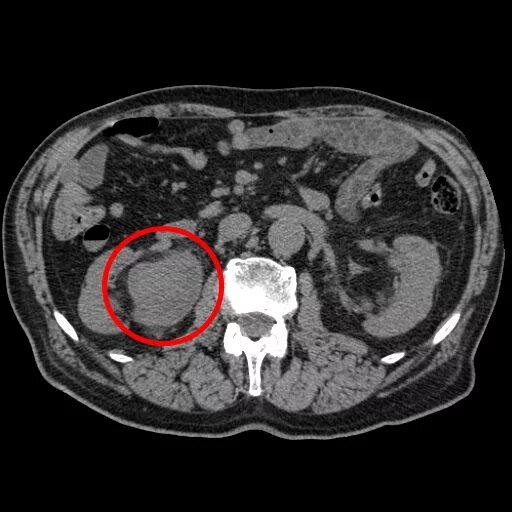

Пиелонефрит кт